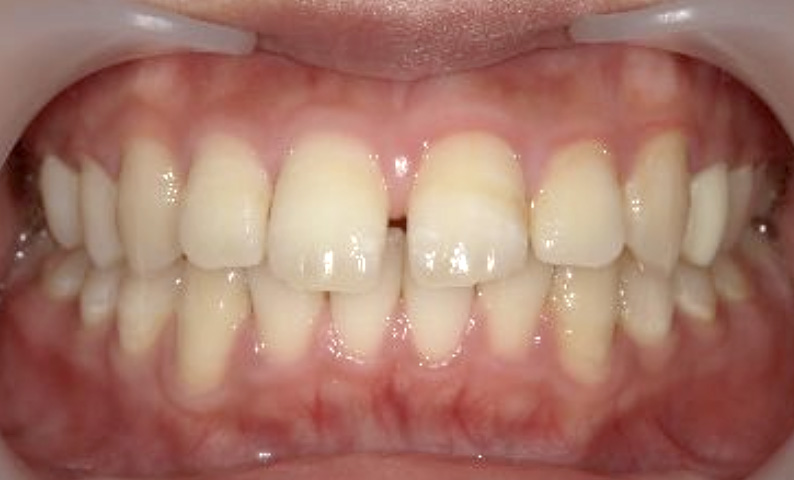

症例_025 上顎だけの部分矯正

治療期間:7ヶ月金額:30万円+税女性前歯のガタガタ上の前歯だけ

| Before | After |